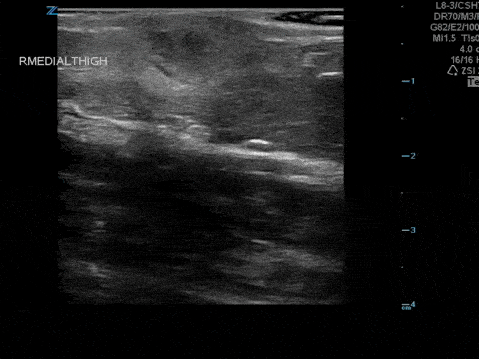

The image above demonstrates a well circumscribed fluid collection within the soft tissue, without evidence of surrounding cellulitis. The above abscess was incised with immediate release of a large volume of purulent material. The patient did well.